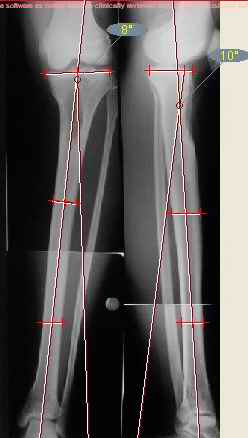

Продолжение обсуждения, начатого в октябре прошлого года (см. здесь) Наконец-то оперировали эту пациентку. Биопсию сделали - опухолевого ничего нет. Пока все участвовавшие в обследовании смежные специалисты и ортопеды сошлись, что это молокальная монооссальная фиброзная дисплазия. 20 марта наложили аппарат, сделали чрескожную остеотомию. К 3 апреля все докрутили. Сегодня заштифтовали. Начальные и итоговые снимки в приложении. Рекурвацию можно было еще немного больше устранить, и чуть кзади сместить диафиз. Но вроде и так ничего выглядит, по сравнению с тем, что было. Комментарии приветствуются.

ничего не понимаю в детской и ортопедии, но в боковой проекции нет рекурвации,

а даже немного гиперкоррекция, что по-моему есть хорошо. Кортикалы по задней стенке совпадают, диафиз на одну неправду кзади.